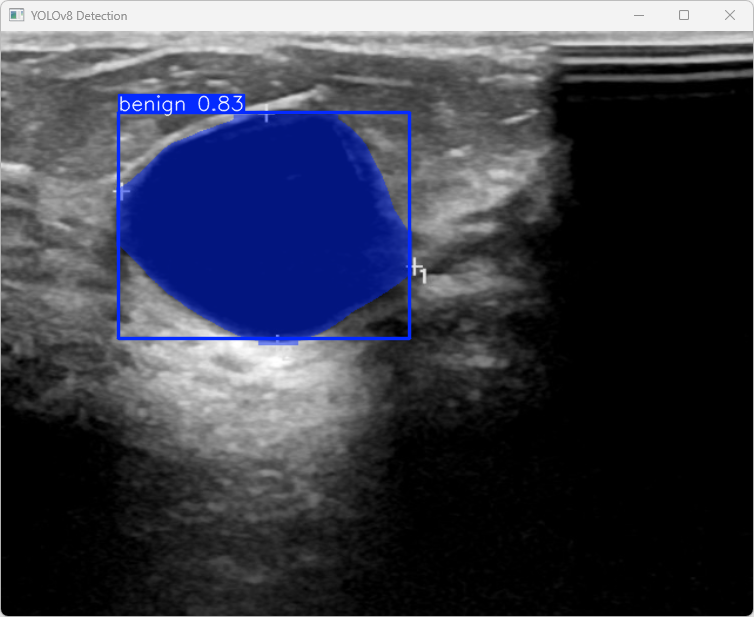

执行imgTest.py代码后,会将执行的结果直接标注在图片上,结果如下:

这段输出利用YOLOv8模型对图片"benign (9).png"进行检测的具体信息如下

图像信息:

(1)处理的图像路径为:TestFiles/benign (9).png。

(2)图像尺寸为512×640像素。

检测结果:

(1)模型在图片中检测到:检测到 1个良性(benign)目标。

处理速度:

(1)预处理时间: 3.5 毫秒

(2)推理时间: 44.1 毫秒

(3)后处理时间: 60.0 毫秒

总结:

模型的分割推理速度较快,整体时间(约107ms)适合实时检测场景。